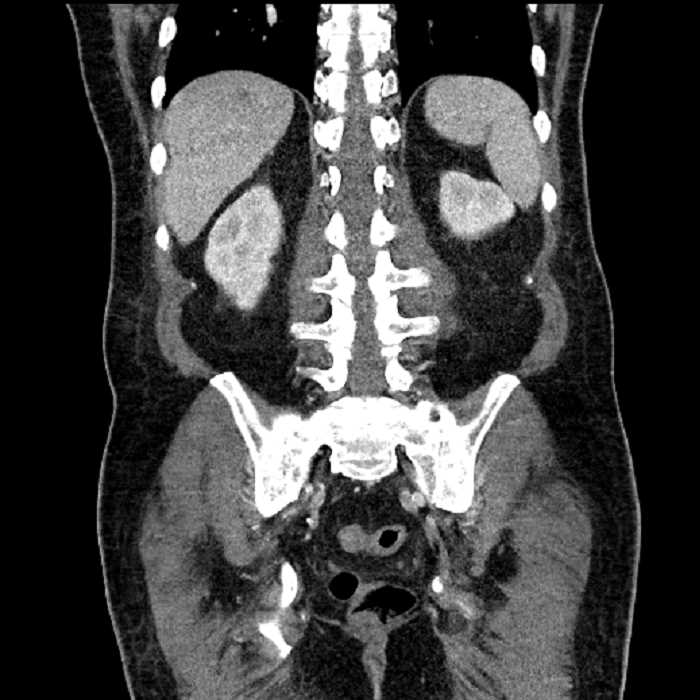

Age: 63

Sex: Male

Indication: Abdominal pain

• Large fluid density structure in hepatic segments 7 and 8 measuring 10 x 7 x 7 cm with internal septation and circumferential ill-defined low density compatible with edema

• Peripherally enhancing subcapsular collections along the anterior margin of the left hepatic lobe measuring 3 x 1 cm and 2 x 1 cm

• Hepatic abscess

Acute sigmoid diverticulitis complicated by a small contained perforation and a large abscess in the right hepatic lobe. Additional small subcapsular abscesses along the anterior margin of the left hepatic lobe.

• The classic CT imaging appearance is a double target sign with internal low density surrounded by an internal enhancing rim (capsule) and a low density external rim (edema)

Hepatic abscess showing the double target sign with low density internally surrounded by a thin inner enhancing rim (red arrow) and ill-defined outer low density rim (yellow arrow). Blue arrow indicates an internal septation. Red arrows: additional smaller subcapsular abscesses. Red arrow: focal contained perforation associated with diverticulitis.